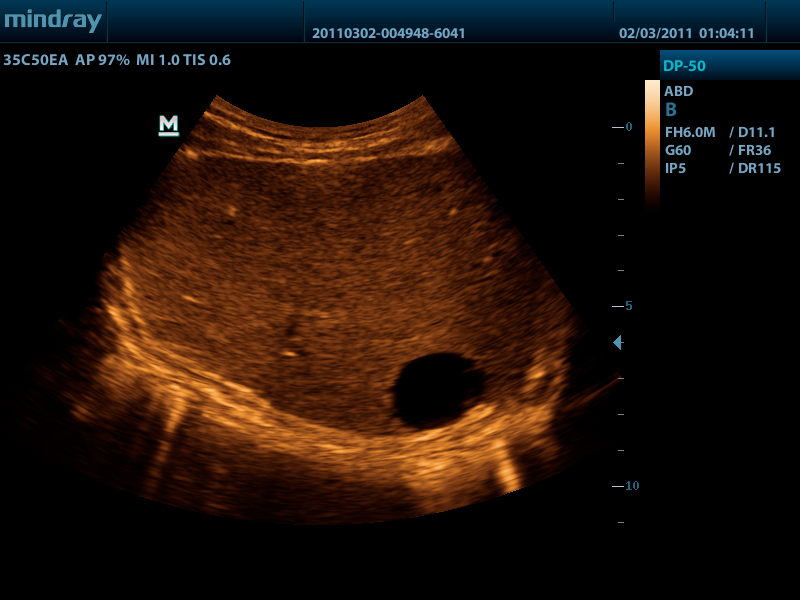

- Конвексный датчик 35C50EA, 1.7 - 6.0 МГц, радиус кривизны 50 мм